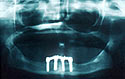

Panoramic radiograph showing the severe atrophy due to long term denture wear.

Surgical placement of four ITI 4.1 and 4.8mm solid screw implants. There were four standard octabutments

placed at the time of surgery and torqued to 35 Ncm.

Final panoramic radiograph